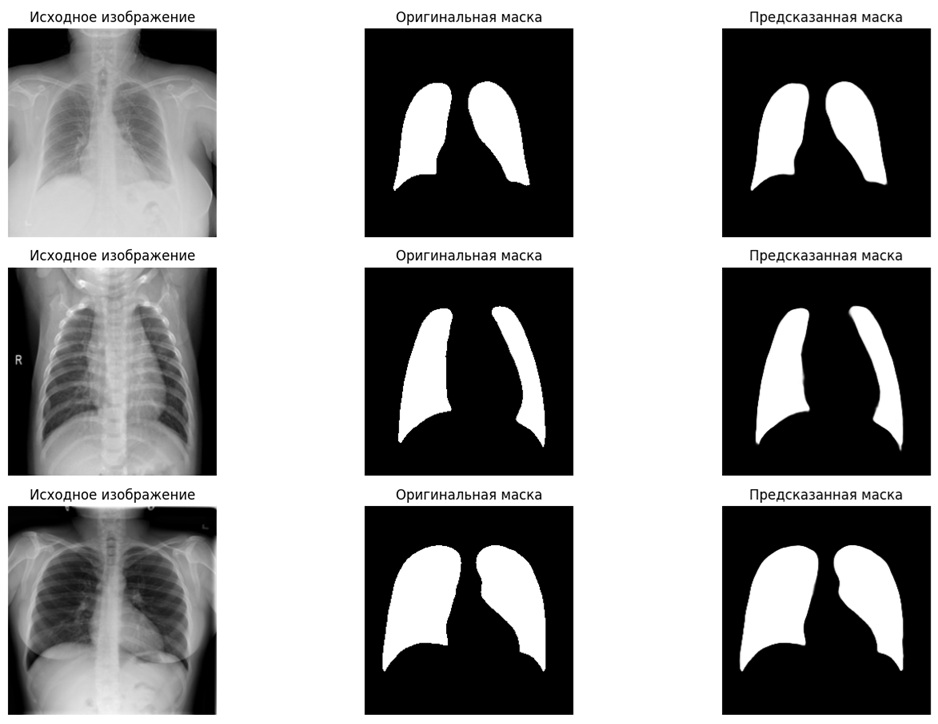

📊Визуализированы результаты, позволяющие сравнить оригинальные снимки, маски и предсказания модели

✅Система стабильно распознаёт границы лёгких даже на сложных снимках

✅Достигается высокая точность сегментации, близкая к экспертной разметке

✅Возможна наглядная проверка качества работы через визуализацию результатов